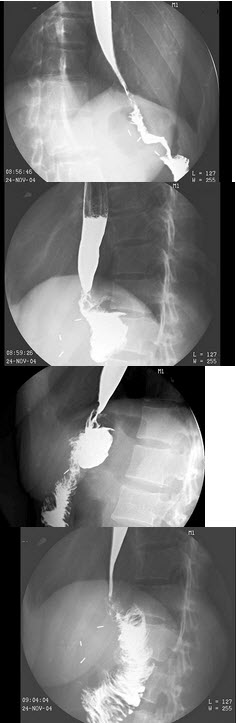

166、单项选择题

男,78岁,进食梗阻2月,结合图像,最可能的诊断为()

A.食管下段癌

B.贲门癌

C.贲门失弛缓

D.胃底癌

E.贲门癌侵及胃底小弯